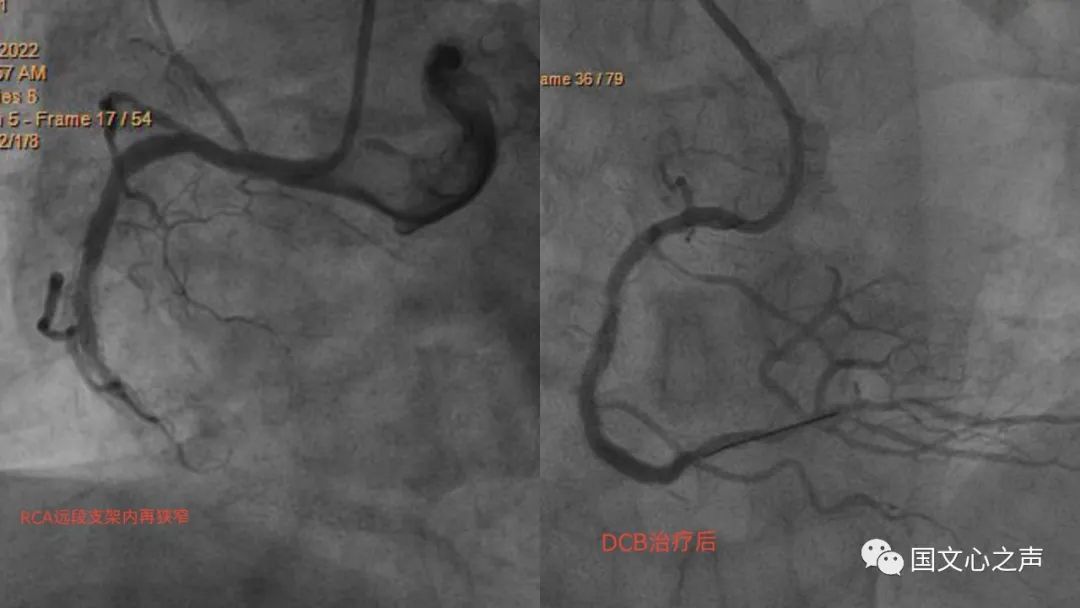

李主任了解到張叔叔的來(lái)意,告知藥物涂層球囊的適應(yīng)癥,便安排其做了冠脈造影,造影結(jié)果提示原來(lái)的右冠脈的支架完全被堵死,這正是藥物涂層球囊治療的適應(yīng)證,征得本人及家屬同意后在病變的支架內(nèi)先應(yīng)用后擴(kuò)張球囊,再應(yīng)用藥物涂層球囊,術(shù)后效果非常好!